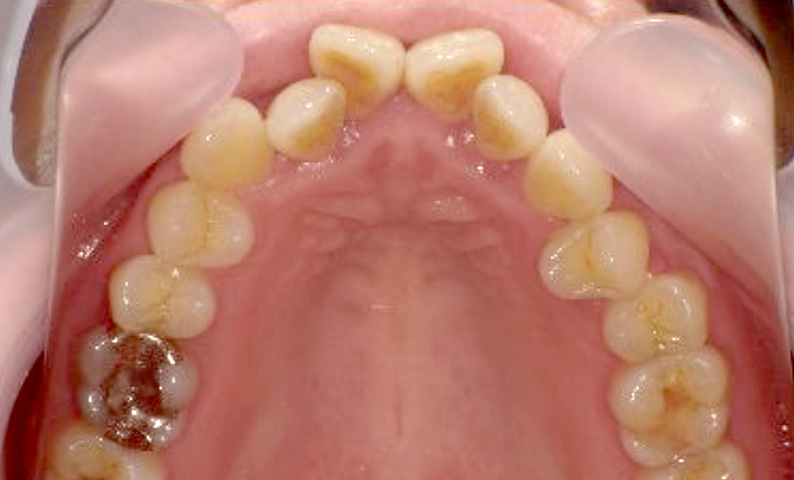

症例_003 下顎だけの部分矯正

治療期間:10ヶ月金額:24万円+税女性前歯のガタガタ下の前歯だけ上顎は補綴治療中

| Before | After |